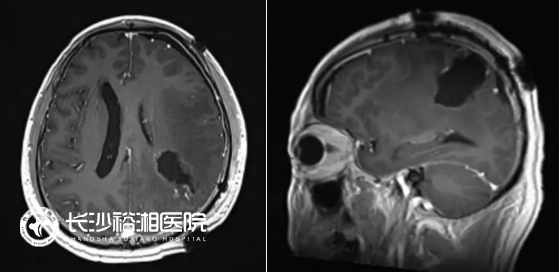

(術(shù)前:頭部增強(qiáng)MRI:左側(cè)額頂葉巨大占位,伴瘤中央壞死,周?chē)笃[,占位效應(yīng)明顯)

(術(shù)后48h內(nèi)MRI提示占位完全切除)